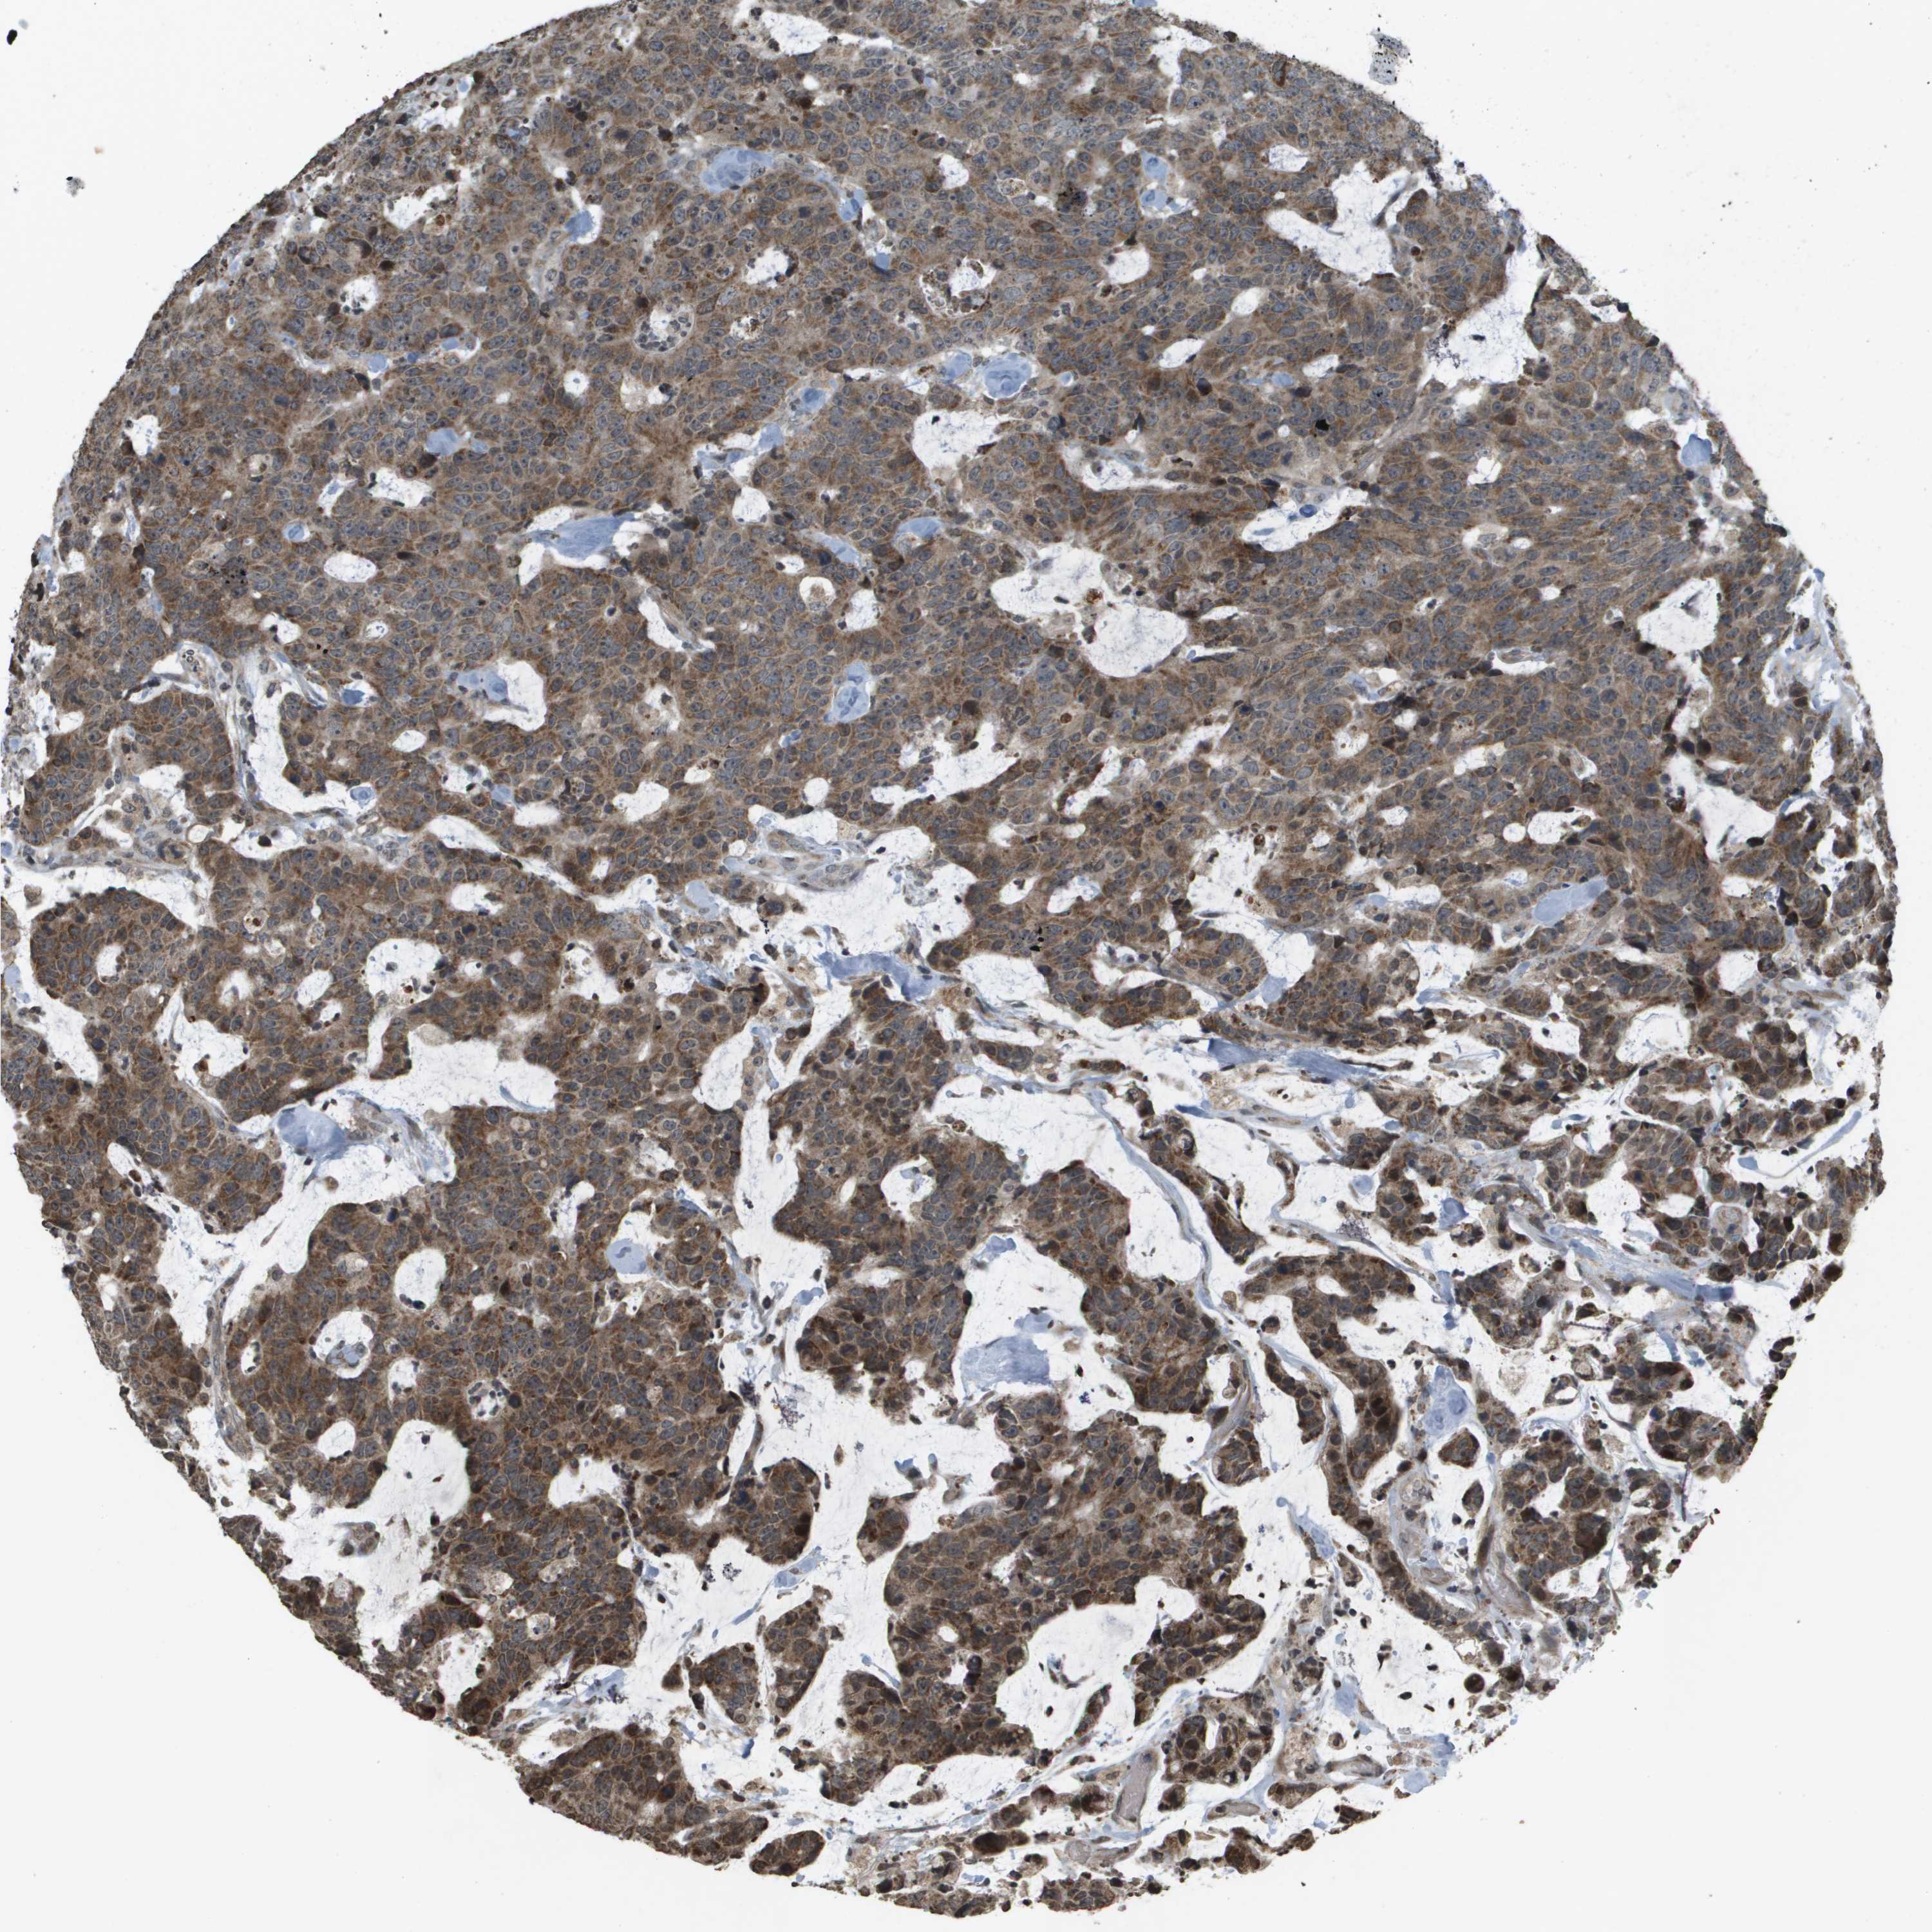

CANCER COLORECTAL CANCER Show tissue menu

Colorectal cancer

Human cancer

Colon adenocarcinoma